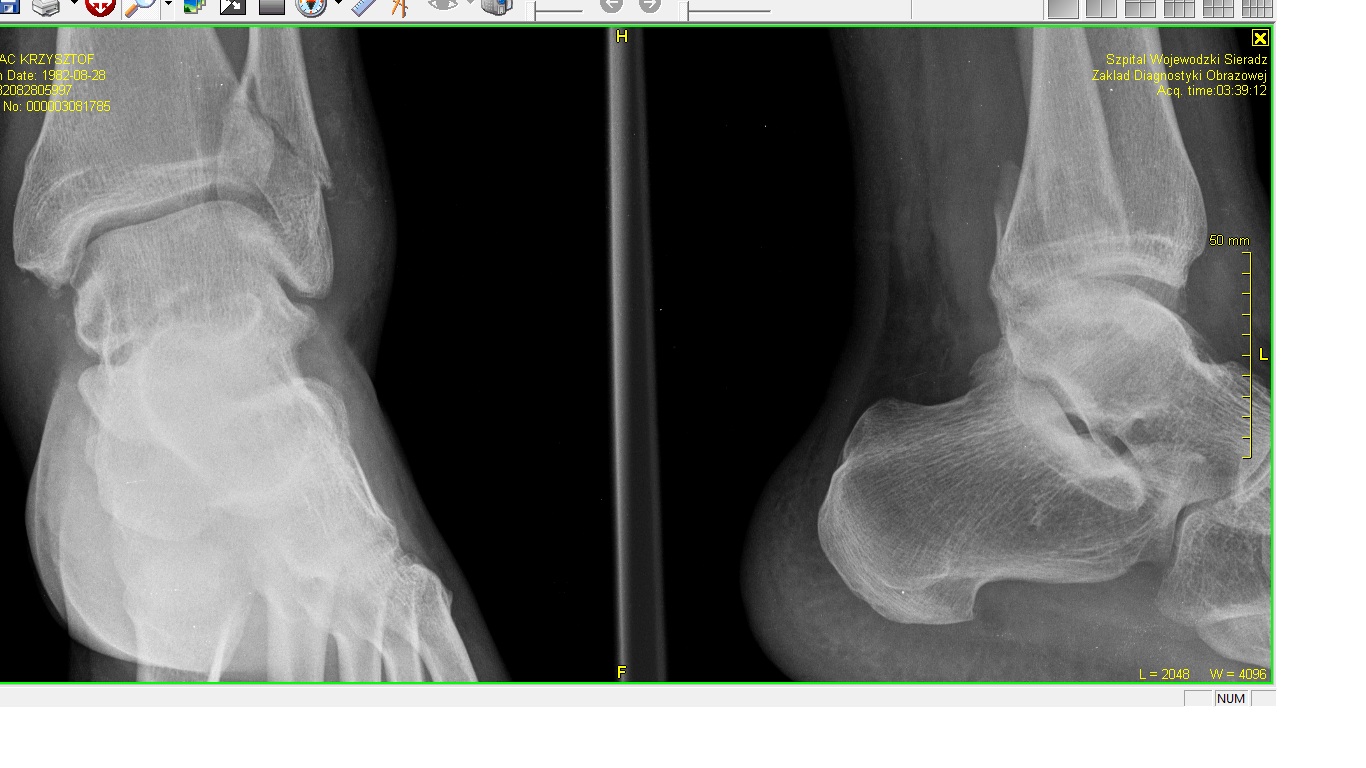

Złamałem kostkę kości strzałkowej, wpakowali mnie w gips ... Wygląda mi to na złamanie z przemieszczeniem, ale może mi się tylko wydaje.

Załączam zdjęcie RTG.

Złamanie.jpg